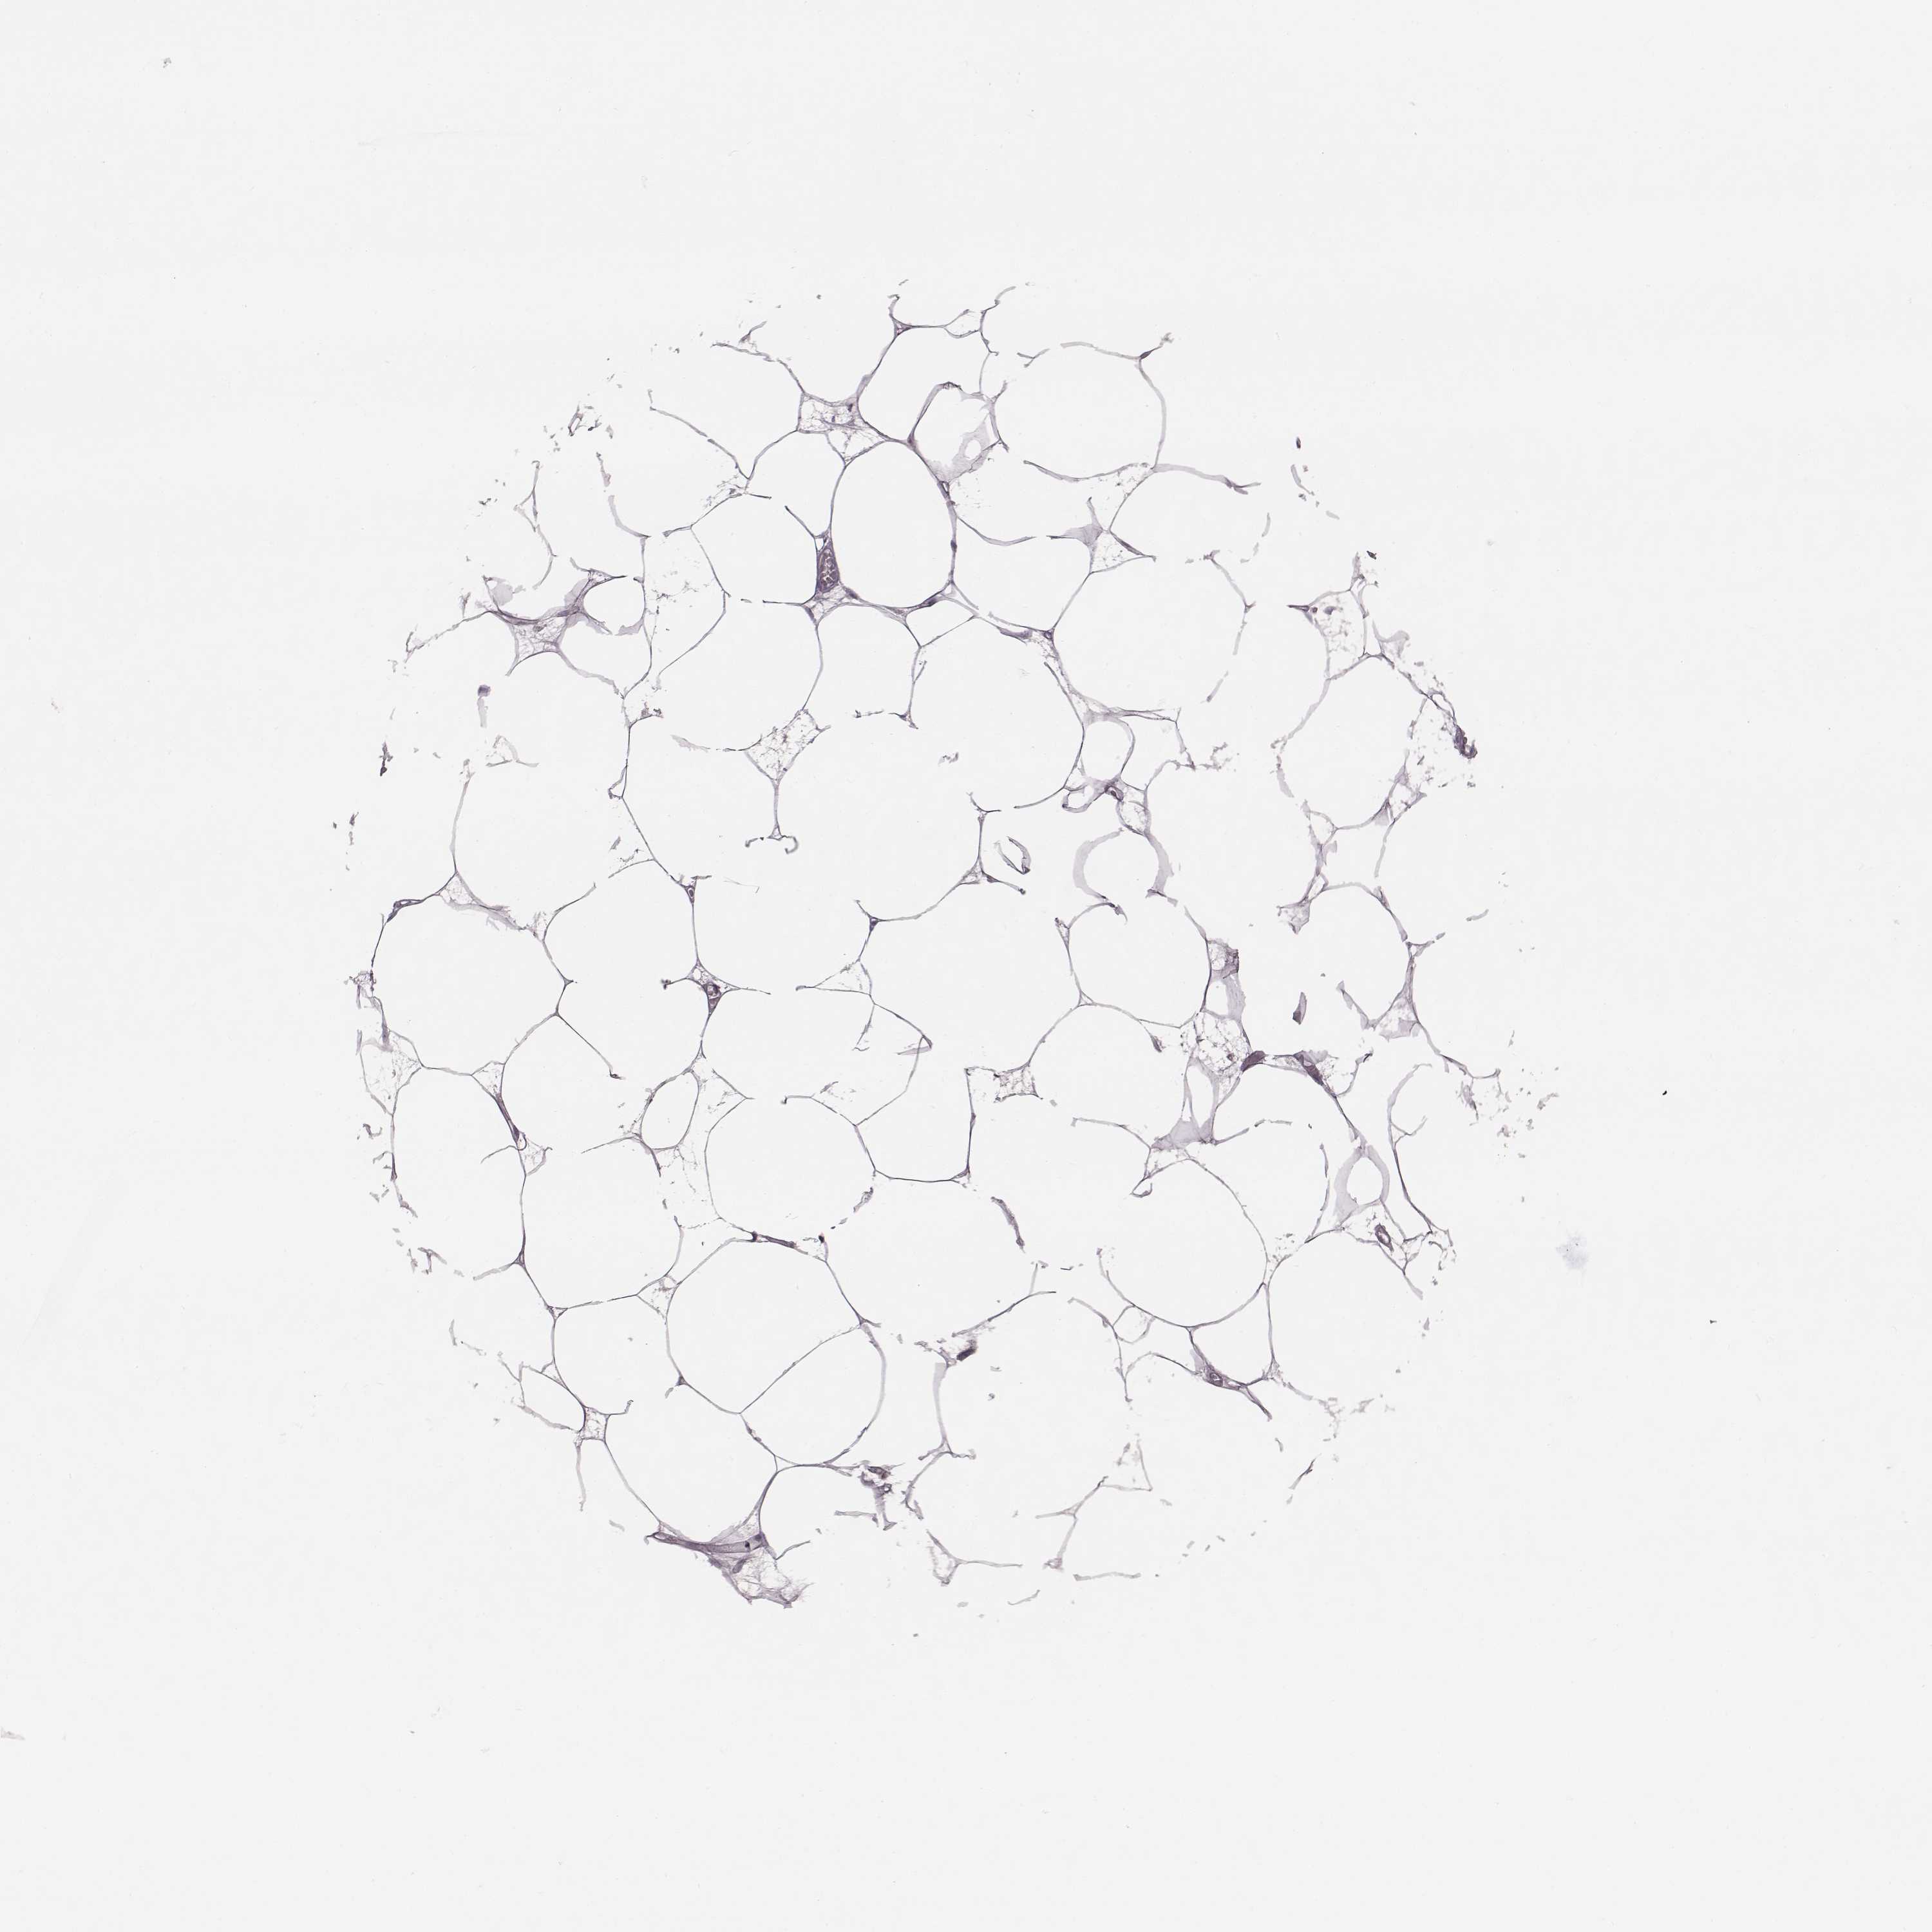

BREAST - Antibody stainingi

Antibody staining in the annotated cell types in the current human tissue is reported as not detected, low, medium, or high, based on conventional immunohistochemistry profiling in selected tissues. This score is based on the combination of the staining intensity and fraction of stained cells.

Each image is clickable and will lead to virtual microscopy that enables deeper exploration of all samples and also displays staining intensity scores, fraction scores and subcellular localization as well as patient and tissue information for each sample.

Antibody HPA069751

Adipocytes Not detected

Glandular cells Not detected

Myoepithelial cells Not detected